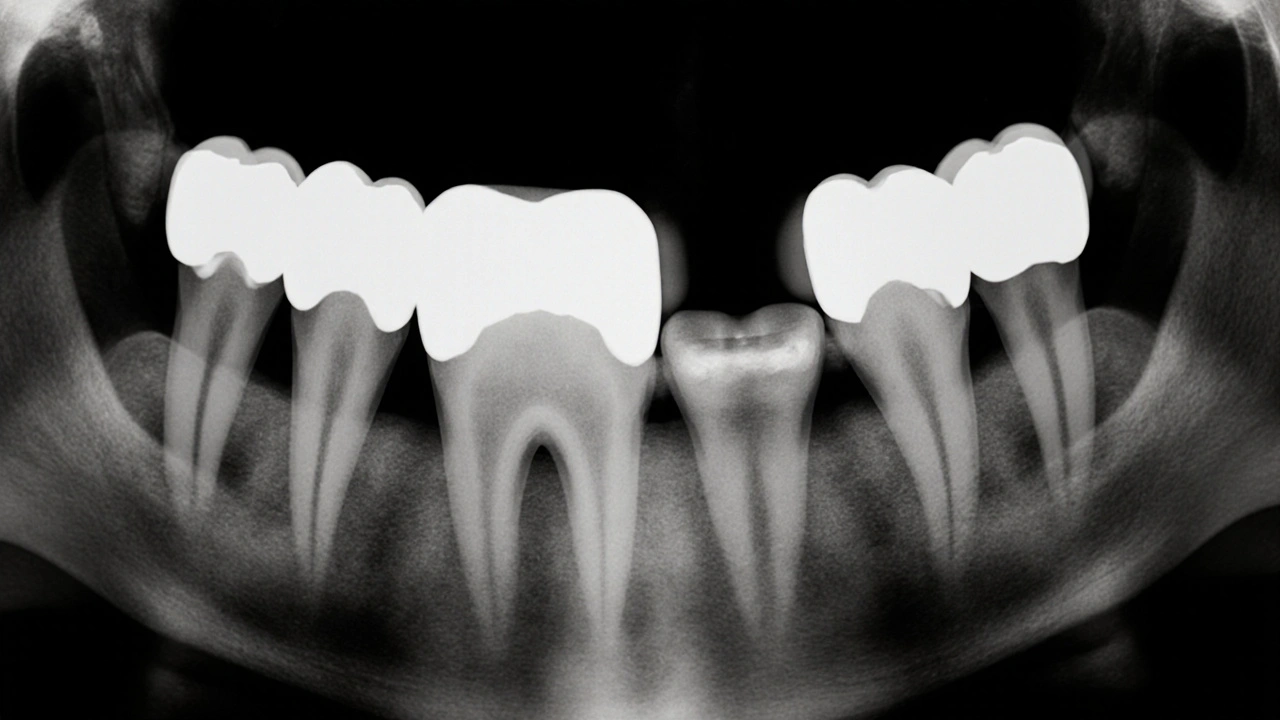

Jak vypadá mezizubní kaz na rentgenovém snímku?

Na běžném panoramatickém nebo bitewingovém rentgenovém snímku vypadá mezizubní kaz jako tmavá šmouha nebo malá dutina mezi dvěma zuby. Zdravá sklovina je na snímku bílá a hustá - jako když se podíváte na bílou dlažbu. Kaz je naopak šedá nebo černá oblast, která vypadá jako „díra“ v zubu. Čím větší je ta tmavá oblast, tím hlouběji se kaz rozšířil.

Na začátku je kaz jen tenká čára mezi zuby - zhruba 1-2 mm široká. To je ještě včas na zastavení. Když se rozšíří na více než 3 mm, už je třeba plombovat. A pokud se dostane až k zubnímu nervu, může být potřeba kořenové léčení nebo dokonce vytažení zubu.